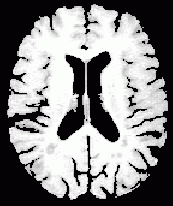

| 6.領域分割 | マスキングとあいまい領域の分割 | ![]() |

| 脳と脊髄:脳体積と萎縮の計測 | ![]() |